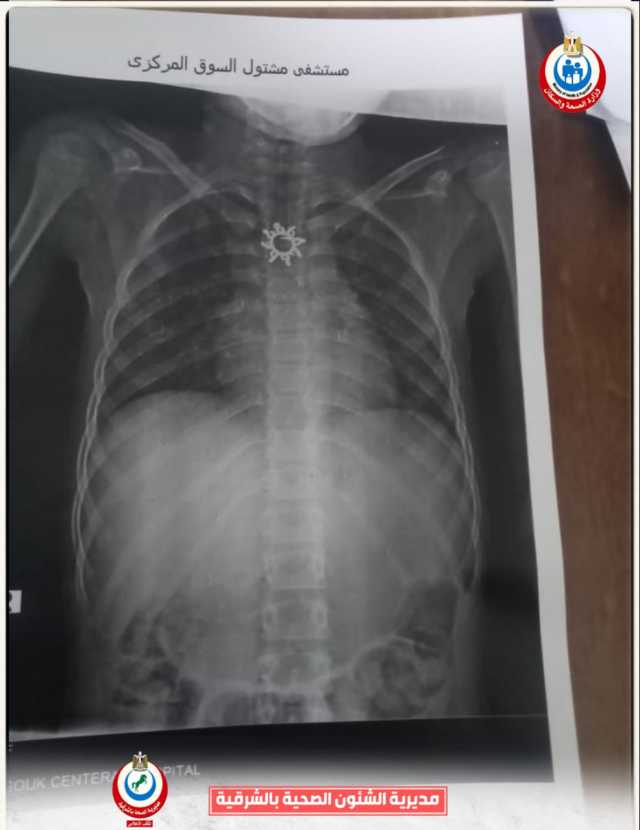

وأوضح الدكتور أحمد البيلي وكيل وزارة الصحة أن قسم المناظير بمستشفى أبو كبير شهد نجاح مميز في إنقاذ الطفلة التي تبلغ من العمر ٥ سنوات، وقامت بابتلاع سلسلة معدنية حادة ومدببة وأطرافها قادرة على إحداث جروح أو ثقوب بالزور أو داخل المعدة، وبعد استقبالها مساء أمس الثلاثاء بمستشفى مشتول السوق المركزي، وتم التنسيق السريع من خلال مركز الخدمات الطارئة ١٣٧ بالمديرية، وتحويل الحالة بسيارة الإسعاف إلى مستشفى أبو كبير في وقت قياسي، وتم التدخل العاجل بالمنظار بعد إجراء كافة الفحوصات الطبية اللازمة لها، واستخراج السلسلة من المعدة دون أي مضاعفات، وسط متابعة وتدخل فوري من الفريق الطبي بقيادة الدكتور محمد عصام خلال الفترة المسائية.